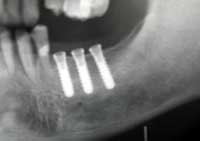

| 術前 | ソケットリフト手術 | 術後2年歯根周囲骨造成良好 |